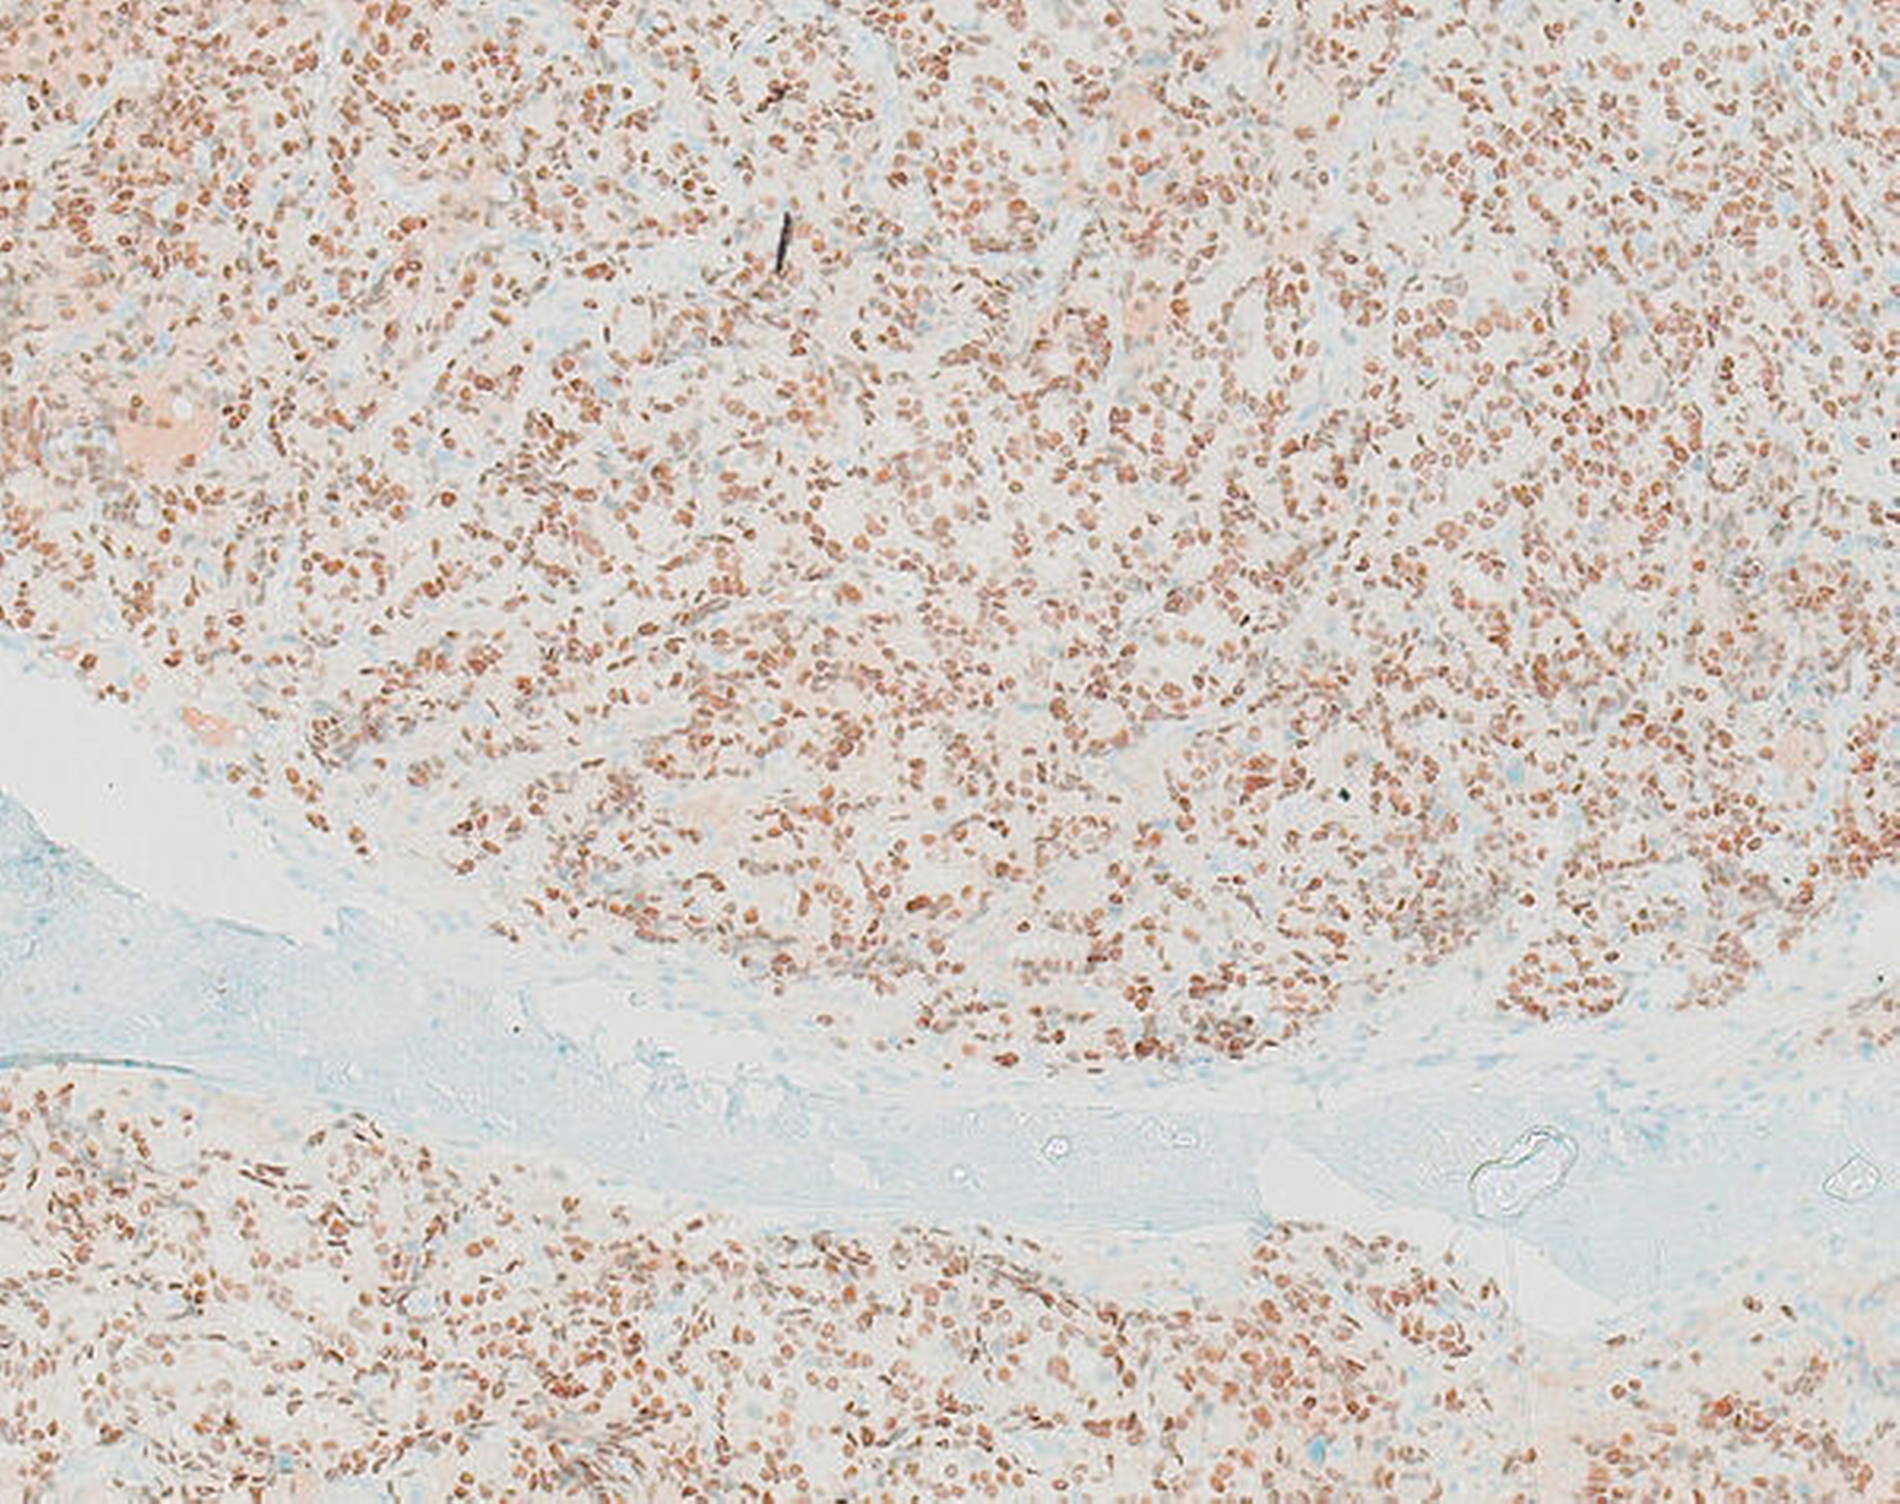

Unter Zusammenschau der schmerzlosen, progredienten Schwellung des rechten Kieferwinkels mit Schleimhautulzeration und nur geringen Entzündungsparametern entschieden wir uns für eine Probenentnahme von intraoral. Die histopathologische Untersuchung ergab, dass es sich um die Metastase eines Adenokarzinoms der Prostata handelt (Abbildungen 2 und 3).